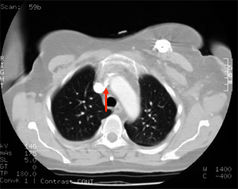

Im Röntgen sieht man den dislozierten Katheter und die Kontrastmittelextravasation ins Mediastinum. Dorthin wurde auch das hochgradig gewebetoxische Adriamycin infundiert.

Thrombosen der Vena subclavia sind symptomarm und werden deshalb fast immer übersehen. Sie sind aber nicht harmlos und oft die Ursache einer Lungenembolie (M.Monreal, A. Ravantos, R. Lerma, J Ruiz, E Lafoz, A Alastrue, JF Llamazares: Pulmonary embolism in patients with upper extremityDVT associated to venous central lines- a prospective study. Thromb Haemost 1994; 72: 548-550).

- Pinch off Syndrom bei 2%. Dabei wird der Katheter zwischen 1. Rippe und Clavicula abgeschert. Es kommt zuerst zur Extravasation bei Injektionen, dann zur Katheterfragmentation mit Embolisation in rechten Vorhof, rechten Ventrikel oder die Lunge. Solange das Katheterfragment noch im Herzen liegt, kann es oft transfemoral mit einer Schlinge extrahiert werden. Aus der Pulmonalarterie kann es nur durch eine offene Operation mit HLM entfernt werden.